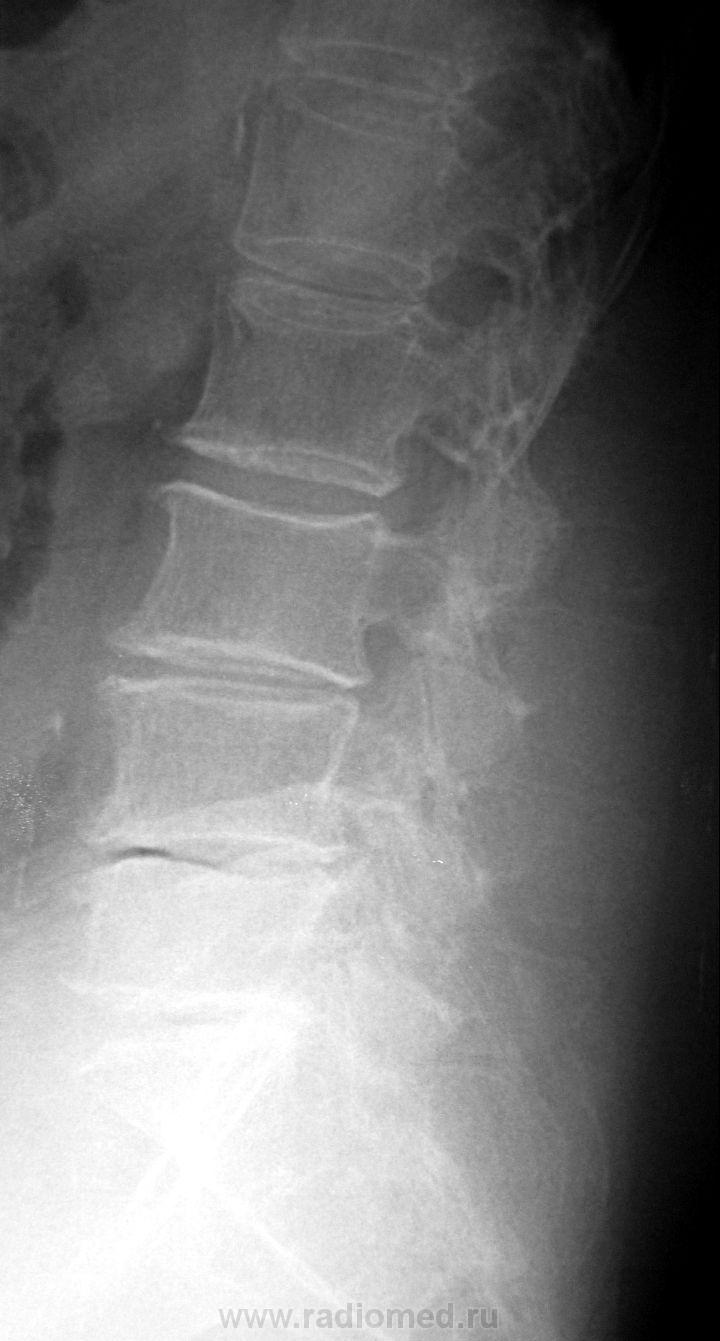

Вот такой пример.....Женщина 72 лет. Жалобы на резкие боли при малейшем движении. Передвигается с трудом.

Как поступить тут? Только описать изменения? Дать собственные выводы?

Мне бы сказали написать дисгормональную спондилопатию компрессионный перлом L2,3?

А L1?...от него почитай ничего не осталось...

А снижение высоты диска L5-S1 с наличием соответствующих изменений позвонков и даже вакуум-феномена?...ведь это из другой оперы...

А проблемы с суставами? - это ведь из третьей оперы...